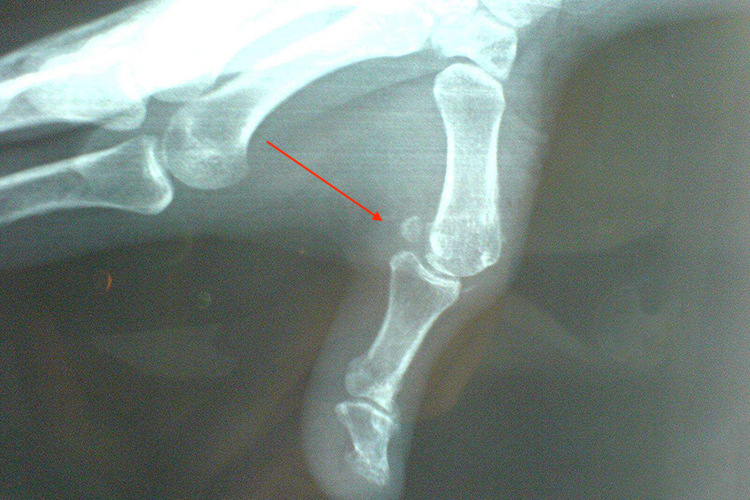

大拇指半脱位主要表现为指间关节未完全脱位,伴有关节局部疼痛、活动障碍。检查时可见拇指肿胀畸形、压痛明显,被动活动时疼痛加剧,且可有明显的弹性固定感。可能伴有侧副韧带断裂或有指骨基底撕脱性骨折。

大拇指半脱位主要表现为指间关节未完全脱位,指间关节为屈戌关节,关节囊的两侧有副韧带加强,脱位的方向多为远节指骨向背侧移位,或内、外侧移位,前方脱位少见。在关节极度过伸、扭转或侧方挤压外力作用时可造成指间关节脱位,有时伴有侧副韧带损伤,严重时侧副韧带断裂,或伴有撕脱骨折。